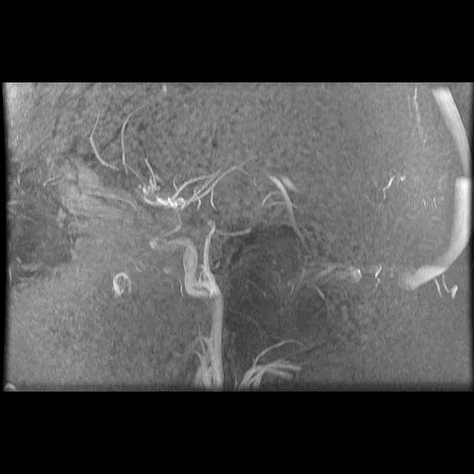

A PET scan is organised a few days later, at St Barts Hospital, in the shadow of St Paul’s. The body is flooded with a tracer radioactive fluid, after which you are locked into a lead-lined box for three-quarters of an hour to allow it to bake in. The scanner then detects where the tracer has been absorbed by cell growth anywhere in the body it is directed, producing reams of flowing light captured to film, copies of which—scans of my own body—are used throughout this post.

The moment I saw the very first scan the doctors showed me (bottom right, above: an MRI, rather than PET, as it happens)—on a small monitor wheeled into my cubicle at the Homerton—seemed to say everything at once. As I turned my head to look at the image of my brain on the monitor, I glimpsed also the tattoo on my left arm suddenly aligned with it (bottom left)—a tattoo of a bhikkhu meditating in flames, inked twenty years earlier, with the bhikkhu meditating as descibed in the Buddha’s Adittapariyaya Sutta (Fire Sermon)—such that the tattoo of the bhikkhu and the scan of the brain, aligned properly. One presaged the other by years, holding out its hand to the other. They reflected each other so neatly, with the tumour in the cerebellum showing up as the red-orange fire bursting through from within, which the bhikkhu sits through.

The wrinkled surface of the cerebral cortex in the scan echoed the Bhavachakra—the wheel of Saṃsāra, of cyclical existence (“Saṃsāra… is a Sanskrit word that means ‘wandering’ as well as ‘world’, wherein the term connotes ‘cyclic change’ or, less formally, ‘running around in circles’)10—against which the bhikkhu rests in the tattoo. Here is an image, not only of that empty time turning that we have talked of, of cyclical return and, dare I say it, reincarnation (though in this formulation, reincarnation is mere repetition, as in the ‘natural’ repetition of pagan society). In the original Fire Sermon, the argument is that the bhikkhu must free themself from the grasping tyranny of the senses. We, on the other hand, will be moving in the other direction. In any case, this combined image almost made me fall out of bed.

On seeing further scans, I recognised, eg., my rib cage as something indeed very much like the frame of Israel’s tents (above, top left), beaming on the shore of the infinite (Blake), but also, in the twisting images of the torso, I am struck by the sprawling energies at play, unleashed by disease. No longer is there the assumed underlying durable person, sealed away from the totality, cybernetically establishing their personal border by fending off and repurposing the chaos, sickness and disorder without. Instead, raw energies start to coalesce, turning Urizenic, mechanical rigidity into flashes, streaks and pulses of contending light.

When looking at the flowing lights of the scans, I am not seeing the regular mechanics/dynamics of fluid flow and the like. It is not the competing power of the different forces involved, sloshing against one another, that impresses. That would represent a reasonable romantic regard for the power of things we don’t fully understand, and which we dimly suspect may outbid us in the end.

What I find more compelling in the forms on show are the signs of a deeper, primordial language of the cosmos, God’s being and the unconstrained underpinning of all those other things, the syntax of God’s mind and its reality of eternal esemplatic (form-giving, creative) inflation. To see the churning faces of the sea of light is to see the surface of the esemplasm that is all being, and which calls us from its depths.